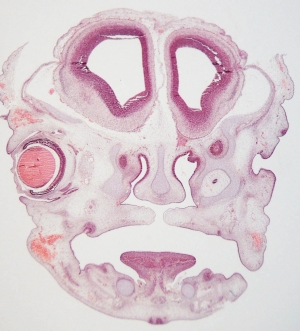

Stage 20

CfS 20

d35-38